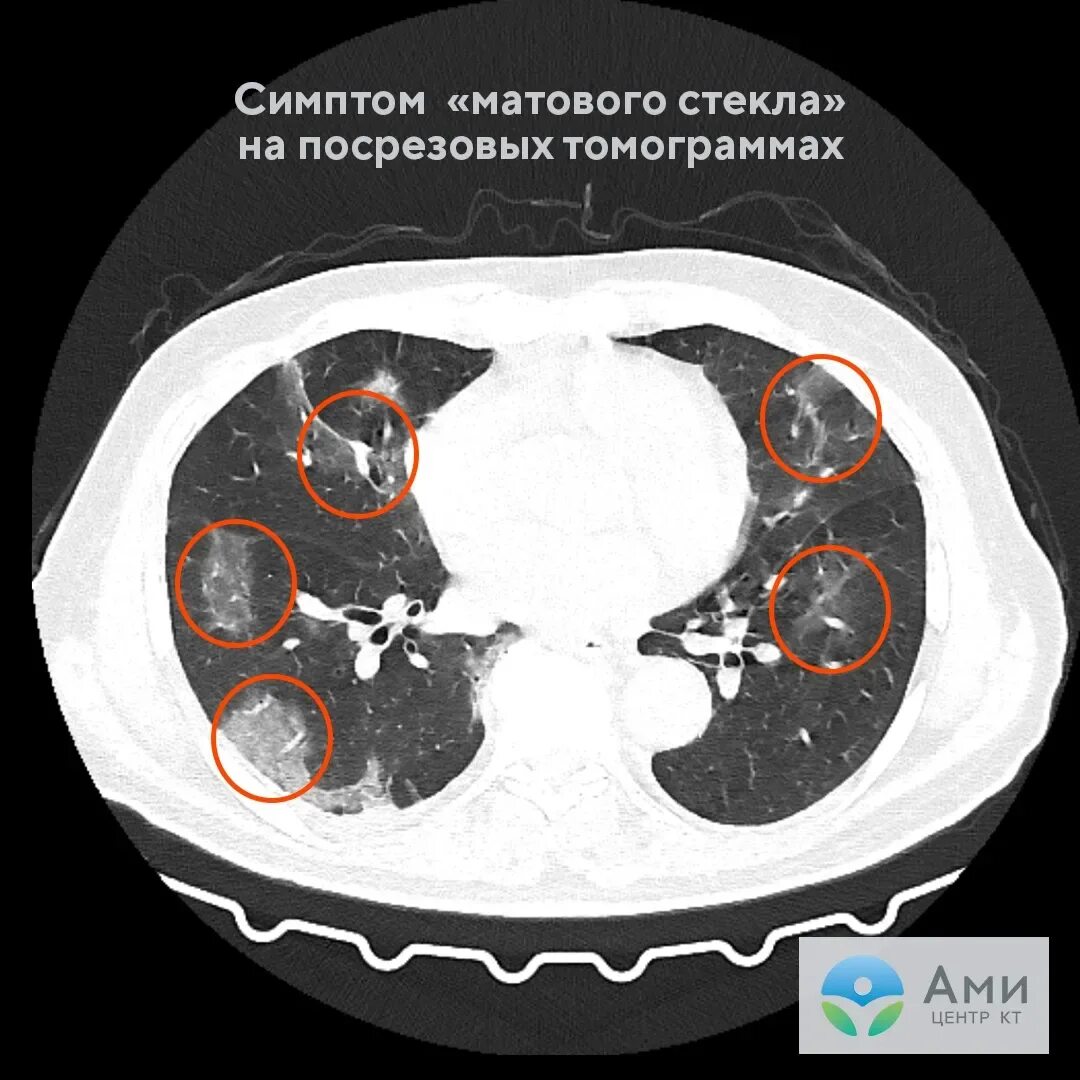

Уплотнения паренхимы по типу